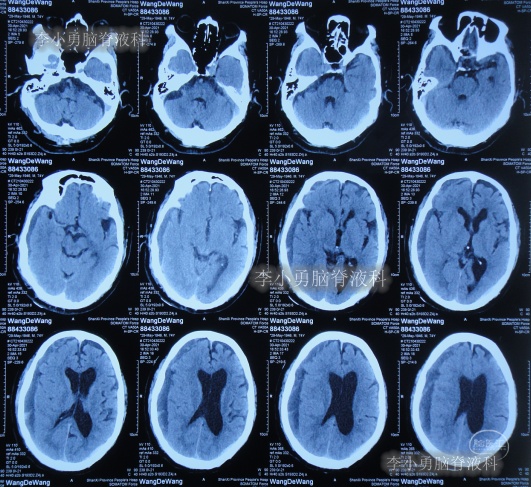

发现脑积水后8天即2020年11月6日,就诊于第2家的上海的某三甲医院,入院后再次检查(图-2)后诊断为正常压力脑积水。

图-2:2020年11月11日头部核磁